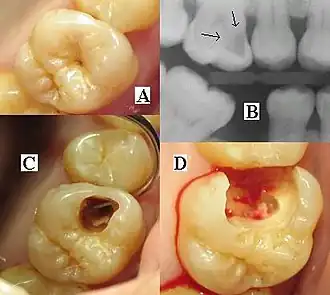

Montage of four pictures: three photographs and one radiograph of the same tooth.

(A) A small spot of decay visible on the surface of a tooth. (B) The radiograph reveals an extensive region of demineralization within the dentin (arrows). (C) A hole is discovered on the side of the tooth at the beginning of decay removal. (D) All decay removed; ready for a filling.